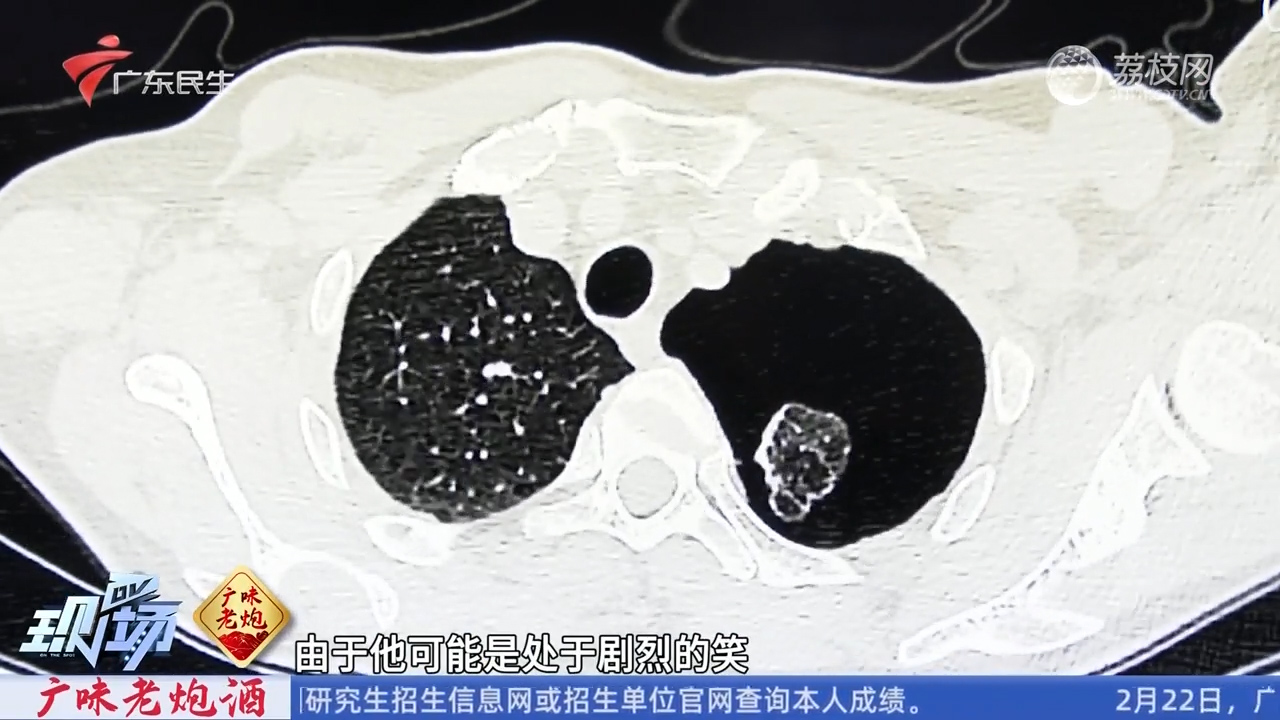

气胸这东西,简单来说就是肺里的空气跑到了胸腔里,把肺给压扁了。听起来就够吓人的吧?更别说那种喘不过气来的感觉了。我那朋友当时脸色苍白,呼吸困难,真是把我吓坏了。

医生说,气胸可能是自发性的,也可能是外伤引起的。不管怎样,一旦发生,就得赶紧处理。我朋友就是及时送医,才没有造成更严重的后果。想想都后怕,要是晚一点,后果不堪设想。